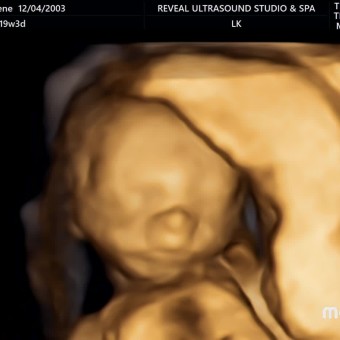

Carene's Baby Registry

Carene Baldwin & James Bates